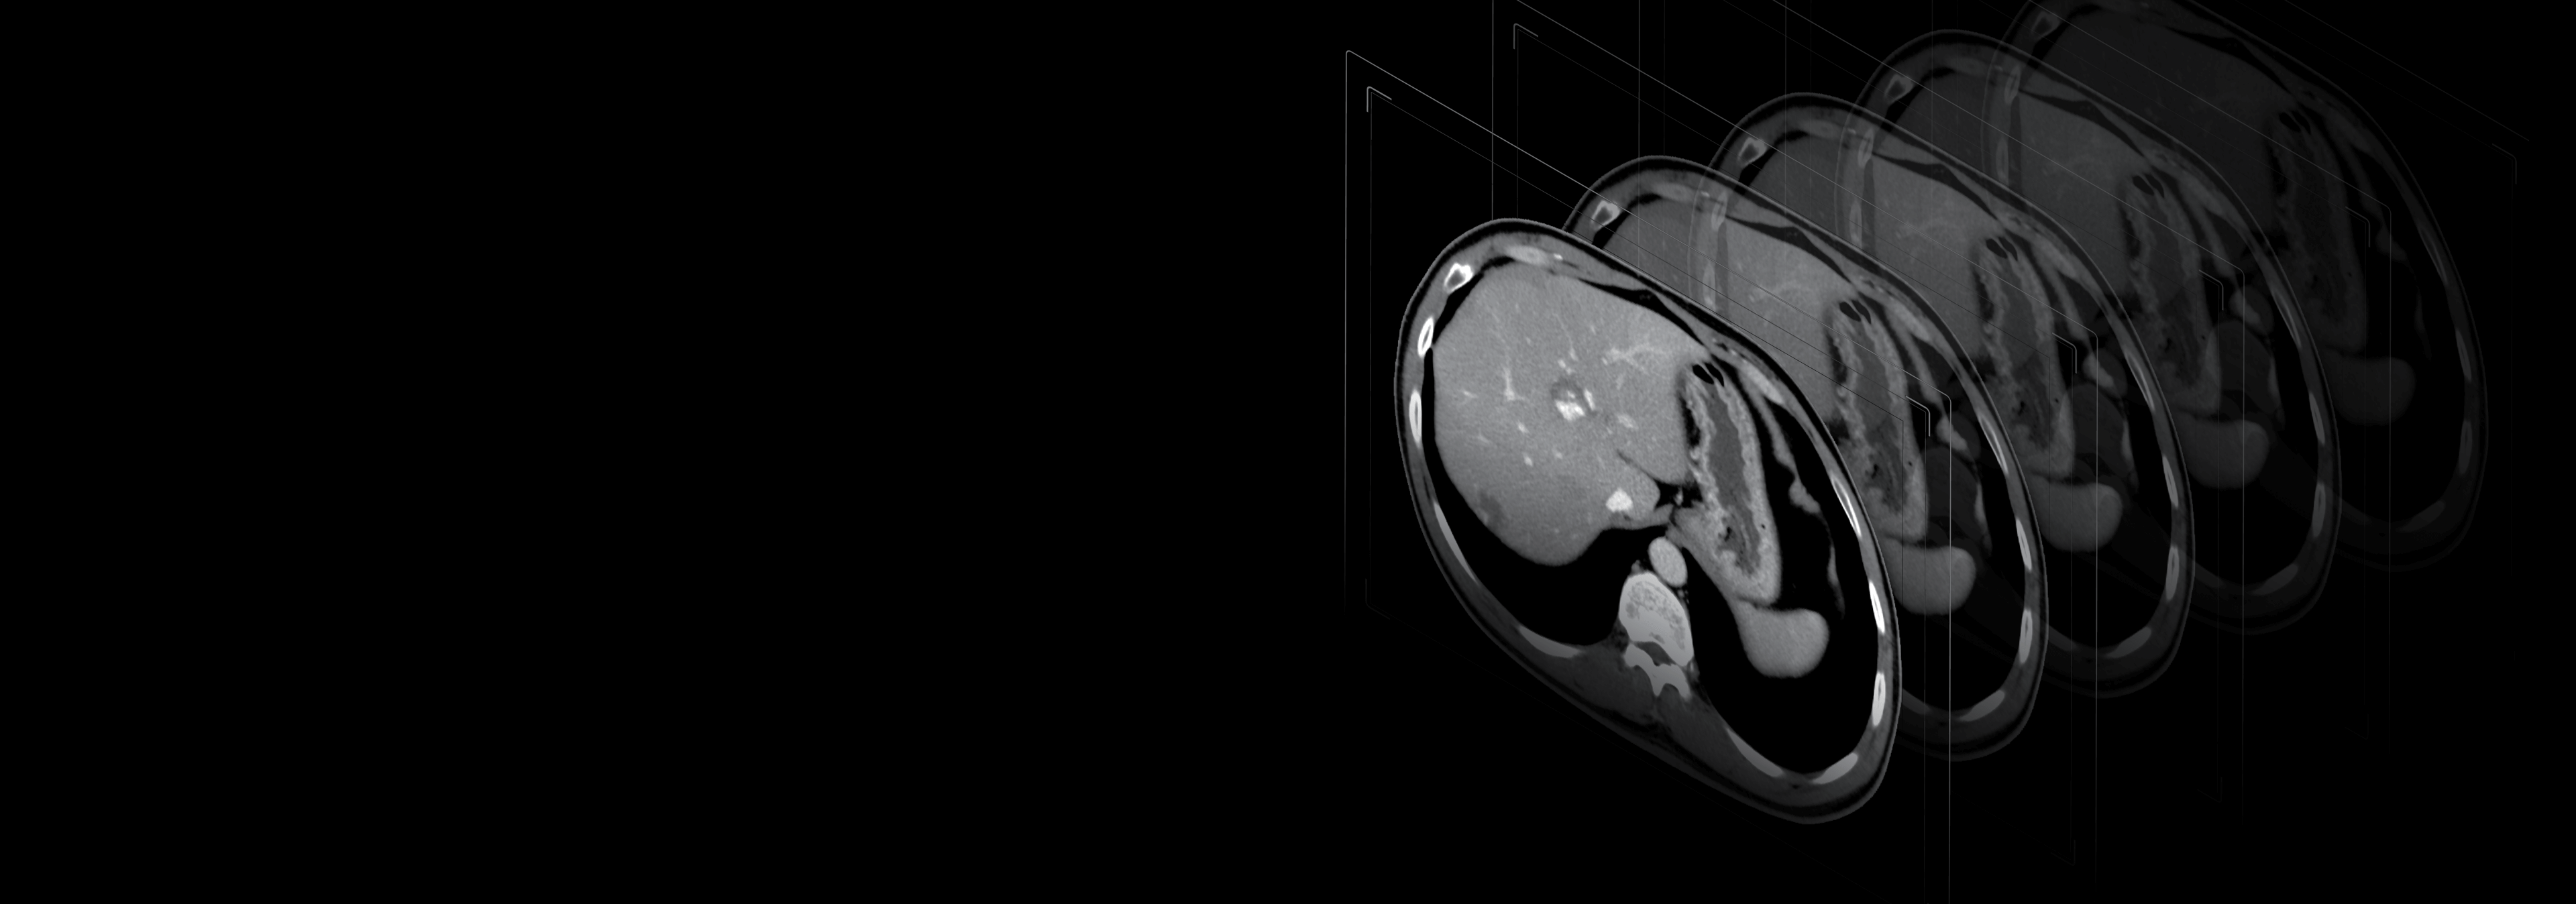

临床应用

头部平扫

头颈CTA

腹部增强

胸部平扫

主动脉CTA

下肢CTA